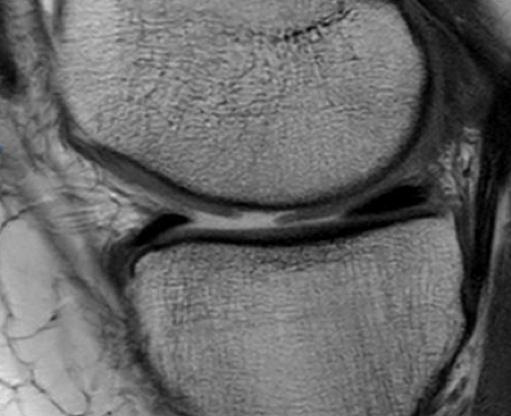

Trasplante osteocondral autólogo para tratar lesiones osteocondrales de la rodilla: evaluación de 62 pacientes con un seguimiento promedio de ocho años. [Osteochondral autograft transplantation for the treatment of osteochondral injuries of the knee: evaluation of 62 patients with an average follow-up of 8 years.]